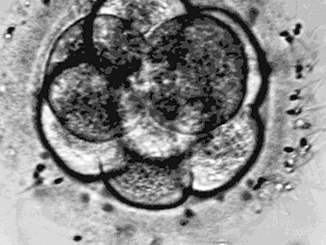

An eight-cell embryo is shown three days after insemination in this undated Eastern Virginia Medical School handout.

An eight-cell embryo is shown three days after insemination in this undated Eastern Virginia Medical School handout.AP